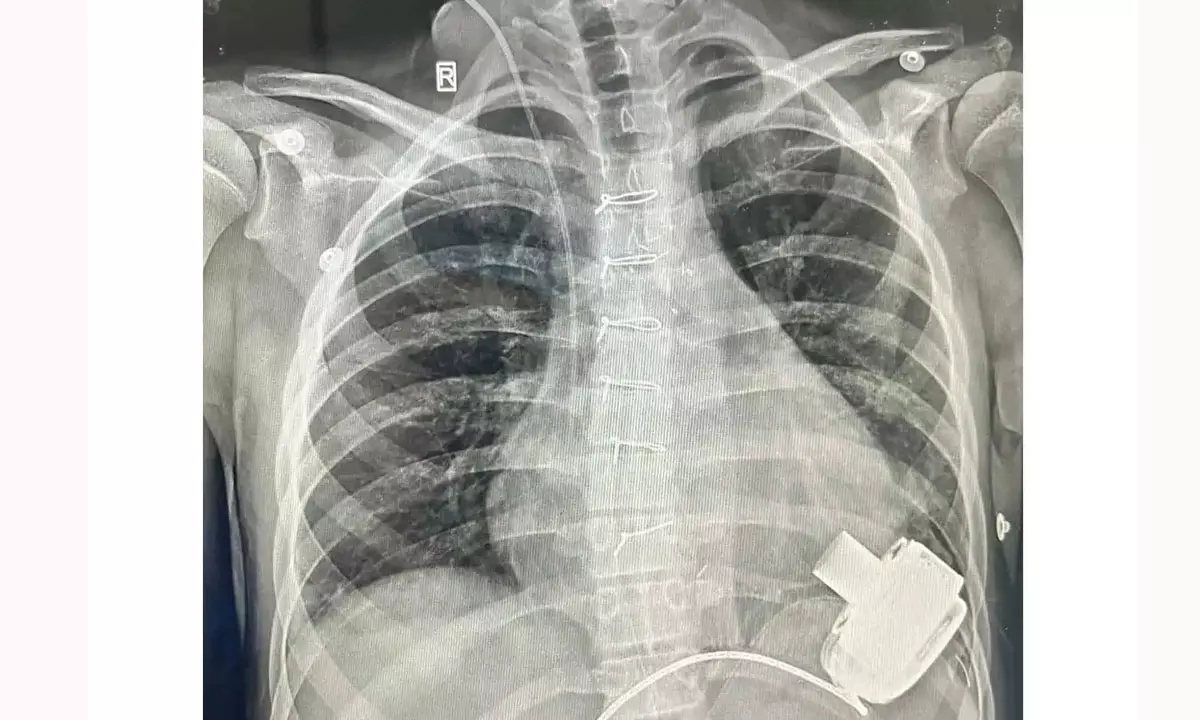

ఉజ్బెకిస్థాన్ బాలుడికి ప్రాణం పోసిన భారత వైద్యులు..